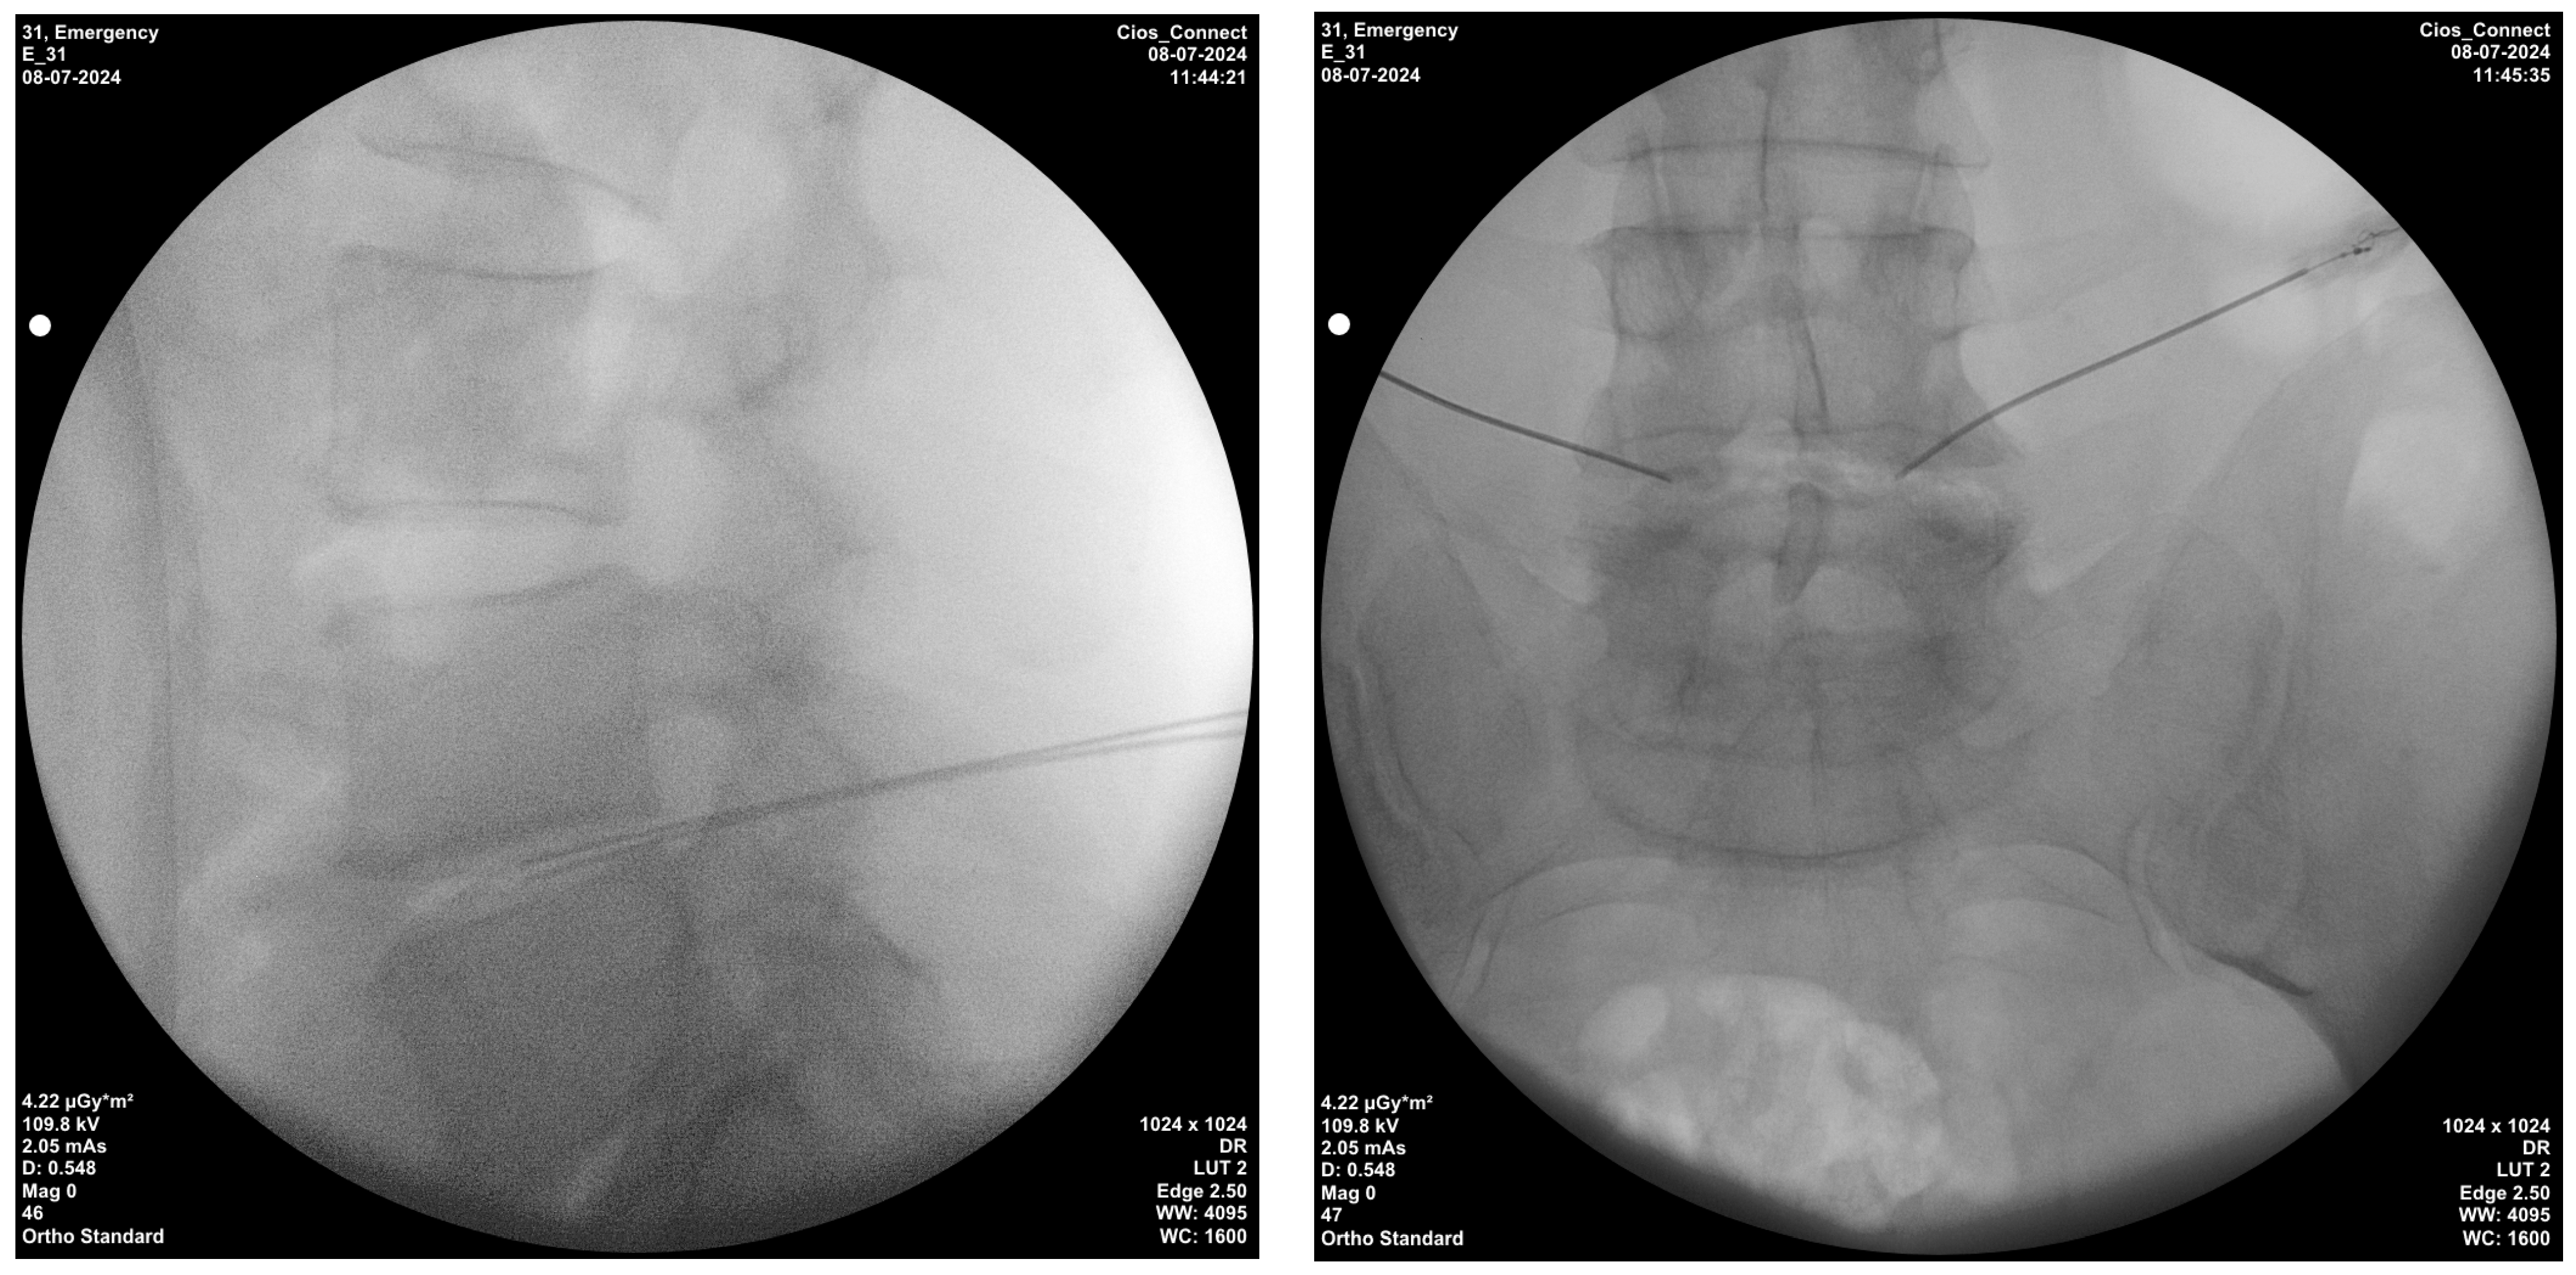

Bipolar radiofrequency thermocoagulation was performed in a sterile room. Sedation was administered to all monitored patients beforehand. Patients placed in the prone position had their treatment area cleaned and covered with a sterile drape, the disc level and entry point where the interventional procedure was performed were localized using C-arm fluoroscopy with the tunnel vision technique. Appropriate disc level and needle placement were confirmed with a posteroanterior fluoroscopic view and advanced, whereas depth was confirmed with a lateral fluoroscopic view (Figure 2). After the procedure, a mixture of 1 mL physiological saline solution and an antibiotic (cephalosporin) was injected into the disc, and the procedure was completed. A 20-gauge, 15 cm needle, and 10 mm active-tip catheter were inserted into the disc. Following a lack of response (no sensory or motor response) to 2 Hz and 50 Hz at 2 V, a lesion was consecutively created at 50 °C for 2 min, 55 °C for 2 min, 60 °C for 2 min, and 65 °C for 4 min using an NT1100 RF generator (NeuroTherm, Middleton, MA, USA) [19].

Figure 2. Techniques of intradiscal bipolar radiofrequency thermocoagulation injection; lateral and posterior–anterior fluoroscopic views.